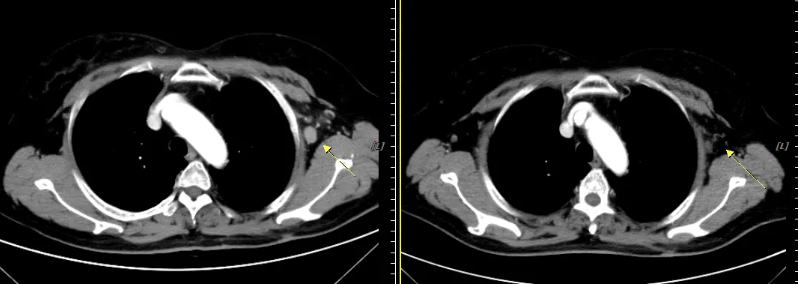

颈部、胸部增强(2019-11)CT示:

食管中下段不规则软组织肿块,考虑食管癌,伴纵隔内、左侧锁骨上、下窝及左侧腋窝、左侧颈根部及胸廓入口处多发肿大淋巴结,考虑转移瘤并侵犯食管上段。

图3 颈部、胸部增强CT(2019年11月)